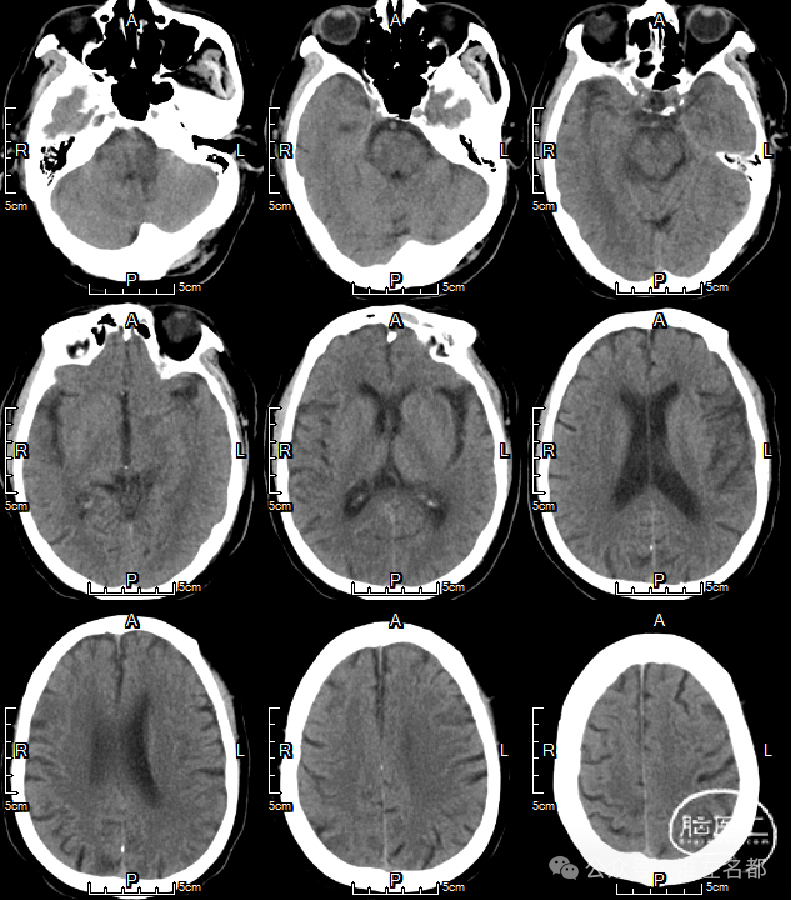

急诊多模式CT

CT平扫:未及明确异常。

颅脑CTA:右侧大脑前动脉A2段局部管腔严重狭窄,右侧大脑前动脉A1段未发育,左侧大脑前动脉A1段粗大。

颈部CTA:所见脑供血动脉未见明确异常。

脑CTP:右侧大脑前动脉供血区局部TTP延长,相应区域CBF和CBV未见明显异常。

复查多模式CT

CT平扫:双侧胼体膝部和右侧额顶叶皮质多发梗死低密度影。

CTA:右侧大脑前动脉原A2段狭窄位置管腔闭塞。

脑CTP:右侧大脑前动脉供血区较大范围TTP显著延长。

CT平扫:少量蛛网膜下腔出血已基本吸收;胼胝体膝部和右侧额顶叶小梗死低密度影。

CTA:右侧大脑前动脉A2局部管腔轻微狭窄。

脑CTP:双侧半球血流灌注基本对称,右侧额叶内侧局部TTP增快。